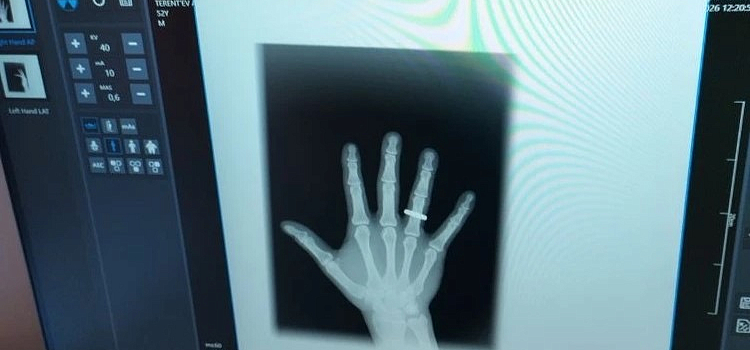

В травмпункте ярославской больницы заработал новый цифровой рентген

Теперь время ожидания снимков сократится вдвое.

В ярославской больнице имени Соловьёва — технологическое обновление. Травмпункт получил современный цифровой рентген-аппарат за шесть миллионов рублей из областного бюджета. Подробностями делится министерство здравоохранения региона.

Новая техника позволит вдвое сократить время ожидания снимков: изображение высокого качества появляется мгновенно, а лучевая нагрузка на пациентов стала минимальной. Учитывая, что в сутки здесь проходят до 300 пациентов, а в месяц — около девяти тысяч, это значительно разгрузит работу медиков в часы пик.

Как рассказала и. о. министра здравоохранения Мария Можейко, обновление травмпункта — часть создания мощного взрослого травматологического центра на базе медучреждения. До этого здесь отремонтировали помещения, открыли дополнительные кабинеты и усилили штат врачей. Оснащение больницы ведётся в том числе в рамках нацпроекта «Продолжительная и активная жизнь».

Фото: министерство здравоохранения Ярославской области